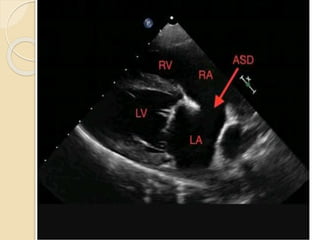

Echocardiography

Echo. Findings…….

 Transthoracic 2D- IAS can be imaged

from apical and subcostal four

chamber view

 Subcostal view is best

 Echo drop out in mid portion for ASD

secundum

 Color doppler imaging shows directly

flow from LA to RA

 2-D echo- echo dropout of interatrial

septum with T sign and left to rt color flow

on color doppler

Echo. Findings…….  Transthoracic2D- IAS can be imaged from apical and subcostal four chamber view  Subcostal view is best  Echo drop out in mid portion for ASD secundum  Color doppler imaging shows directly flow from LA to RA